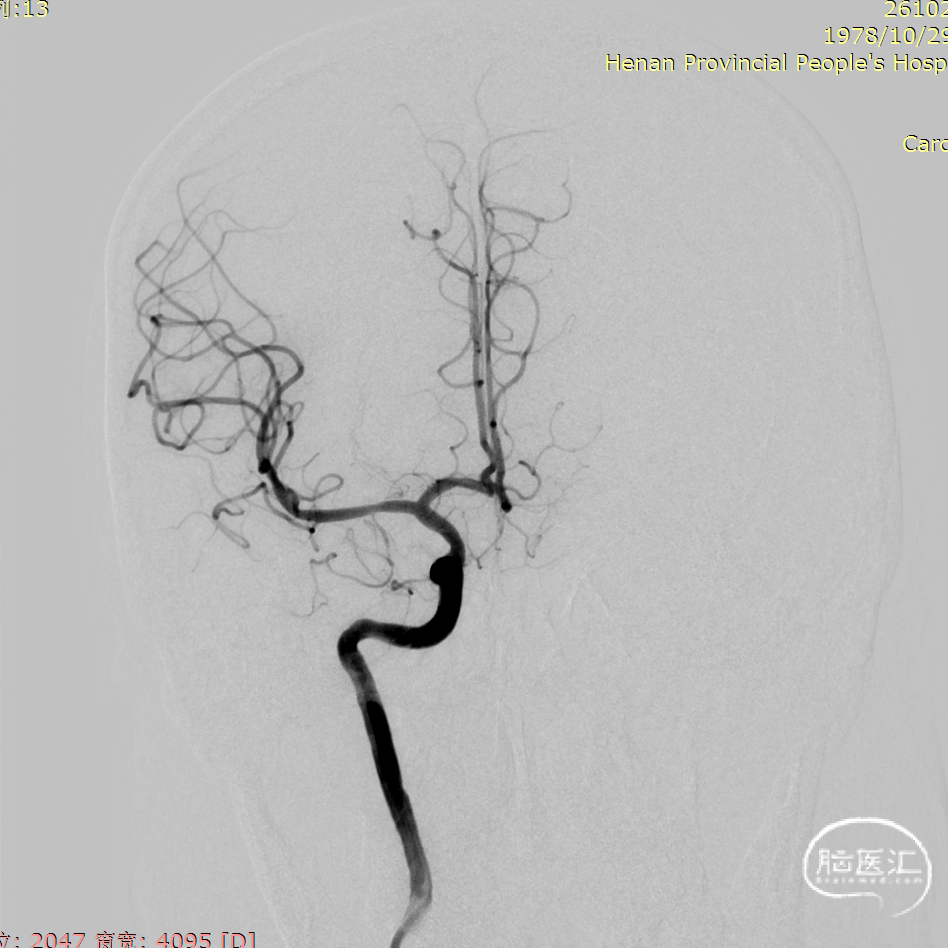

入院后DSA提示右侧大脑中动脉充盈缺损,考虑夹层可能大。

术前讨论

1、右侧大脑中动脉狭窄。

2、脑梗死。

右侧大脑中动脉支架成形术。